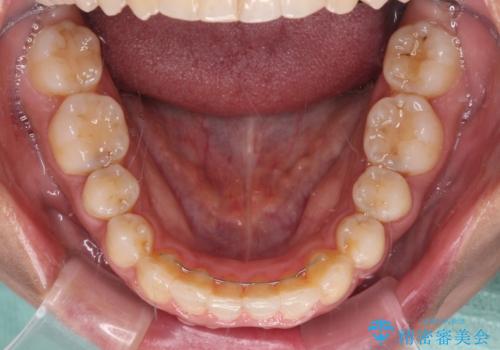

沖縄から飛行機で通院 インビザラインによる矯正治療

- 患者様

- 30代女性

- 矯正装置

- インビザライン

- 治療期間

- 3年8ヶ月

- 定期的に東京に来るので、沖縄から矯正治療で通院したいとのことで来院された患者様です。

歯列不正は軽度であったので、応急処置の少ないインビザラインにて矯正治療を行うこととしました。